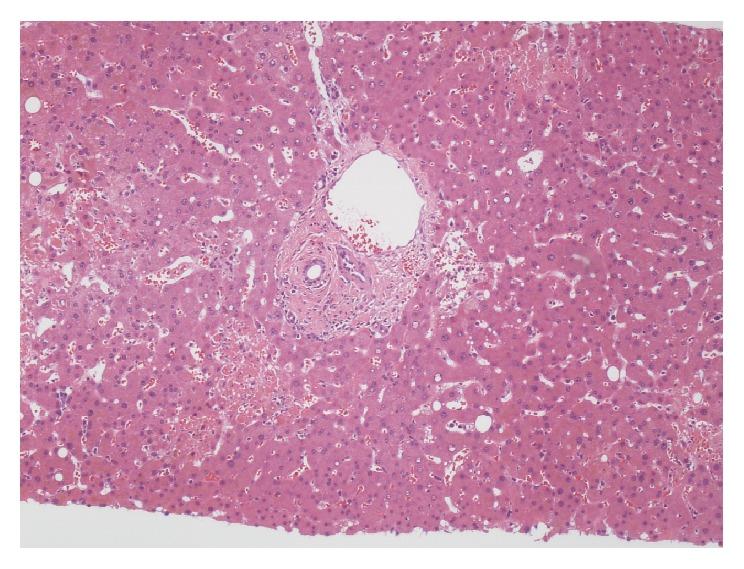

Acute liver failure (ALF) can be due to numerous causes and result in fatality or necessitate liver transplantation if left untreated. Possible etiologies of ALF include ischemia, venous obstruction, medications, toxins, autoimmune hepatitis, metabolic and infectious causes including hepatitis A-E, varicella-zoster virus (VZV), cytomegalovirus (CMV), herpes simplex virus (HSV), Epstein-Barr virus (EBV), and adenovirus with VZV being the most rarely reported. Pathognomonic skin lesions facilitate diagnosis of VZV hepatitis, but definitive diagnosis is secured with liver biopsy, tissue histopathology, culture, and specific VZV polymerase chain reaction (PCR). Antiviral treatment with intravenous acyclovir can be effective if initiated in a timely manner; however, comorbidities and complications frequently result in high mortality, especially in immunocompromised hosts as exemplified in this case presentation.

急性肝衰竭(ALF)可由多种原因引起,若不治疗可导致死亡或需要进行肝移植。ALF的可能病因包括缺血、静脉阻塞、药物、毒素、自身免疫性肝炎、代谢及感染性病因,其中包括甲型至戊型肝炎、水痘-带状疱疹病毒(VZV)、巨细胞病毒(CMV)、单纯疱疹病毒(HSV)、爱泼斯坦-巴尔病毒(EBV)和腺病毒,VZV是报道最少的。特征性皮肤损害有助于VZV肝炎的诊断,但肝活检、组织病理学、培养及特异性VZV聚合酶链反应(PCR)可确诊。若及时开始静脉注射阿昔洛韦进行抗病毒治疗可能有效;然而,合并症和并发症常导致高死亡率,尤其是在免疫功能低下的宿主中,本病例报告即为例证。